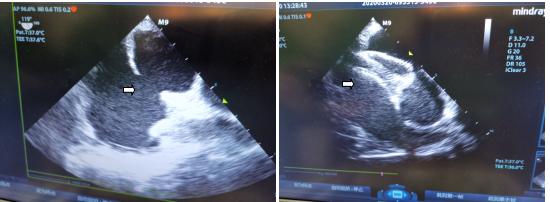

程颖主任带领下的心胸外科团队在老杜右侧胸壁做了个3cm的小切口,在超声科医师食道超声的引导下,经右心房在老杜心脏中顺利植入了一枚30mm的房间隔缺损封堵器。

术中食道超声及术后的经胸壁超声监测都显示出封堵器固定位置、形态良好,未见房间隔残余分流,估测肺动脉压由封堵前57mmHg降至封堵后38mmHg。听诊心脏杂音消失,手术顺利完成。

术中食道超声监测截图,左箭头所指为房间隔缺损,右箭头所指为封堵器。